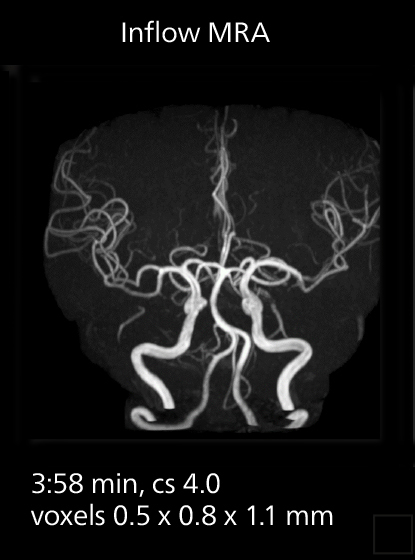

Diffusion studies benefit from powerful gradients

The high performance of the Vega HP gradients is particularly impressive in DWI. “The Vega HP gradients enable us to scan faster and use b-values as high as 2000, for example in prostate DWI and in DWIBS, which provides image quality that is remarkably improved over the previous system and we are able to more easily see lesions.”